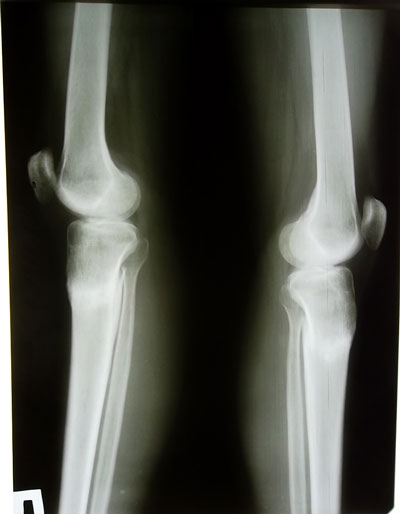

7 месяцев с момента операции и 3,5 месяца после снятия аппаратов.

Рентгеновские снимки через 3,5 месяца после снятия аппаратов.

Регенерат мощнейший, никаких ограничений нет, каблуки любой величины разрешили.